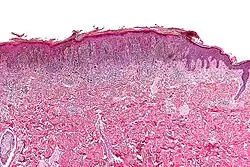

| Micrograph of a pigmented spindle cell nevus (top of image). H&E stain. | |

A pigmented spindle cell nevus is a skin condition characterized by a dark brown to black macule or papule, usually less than 6 mm.[1]